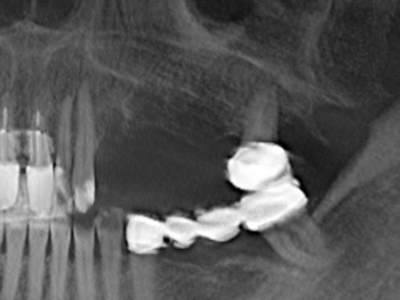

Indication: Preparation near nerves

Indication: Apical resection

When surgical procedures are performed on bone in the immediate vicinity of sensitive structures such as blood vessels or nerves, rotary instruments pose a significant risk of iatrogenic injury. Piezoelectric devices can be helpful for preparation of bone covers and removal of hard tissue close to nerves, particularly for exposure of nerves after iatrogenic injury but also during nerve lateralization for resective and reconstructive procedures or implant placement (Fig. 17-20). Light contact between the piezotip and the nerve does not generally result in damage but proceeding incautiously with saw-like motions or attachments where a residual bone substrate remains may cause temporary or even permanent nerve damage. However, the risk of damage is considered to be substantially lower than when using saws or milling instruments (Pereira, Gealh et al. 2014).